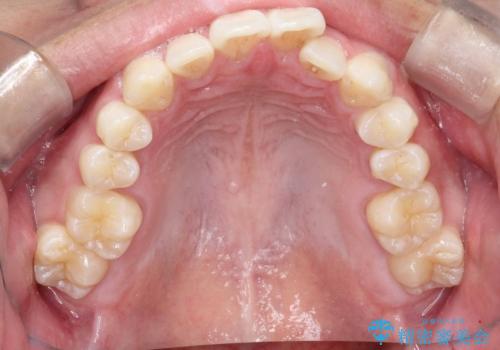

- 歯のデコボコと過蓋咬合を主訴に来院された患者様です。

アーチの拡大とIPRを行い非抜歯で治療を行いました。

歯を抜かずに叢生(デコボコ歯列)と過蓋咬合を改善する事が出来ました。

インビザラインによる治療でも十分に美しい歯並びを実現でき、患者様にも大変ご満足いただけました。